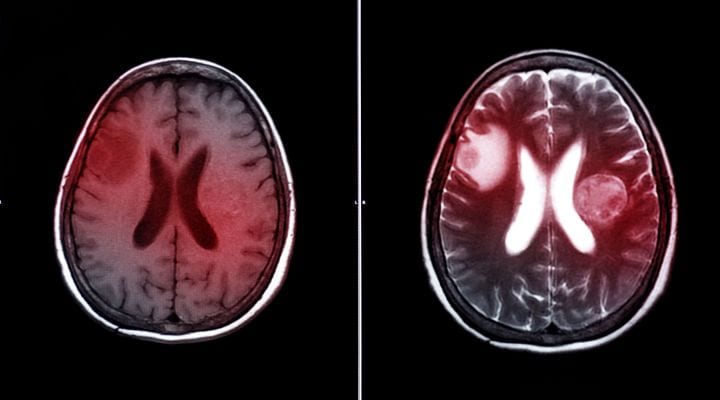

Οι όγκοι εγκεφάλου δημιουργούνται λόγω του ανεξέλεγκτου πολλαπλασιασμού των κυττάρων του ίδιου του εγκεφάλου, των μηνίγγων, του αδένα της υπόφυσης ή των κρανιακών νεύρων. Διακρίνονται σε πρωτοπαθείς ή δευτεροπαθείς, καλοήθεις ή κακοήθεις. Ανάλογα με τη θέση που εντοπίζονται, την ιστολογική σύσταση, το μέγεθος, την ηλικία του ασθενή και την κλινική εικόνα που παρουσιάζει αντιμετωπίζονται είτε χειρουργικά είτε συντηρητικά.

- Μαγνητική και αξονική τομογραφία